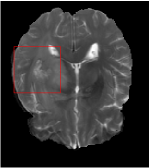

All the experiments are implemented on a Windows workstation with Intel Core i9 CPU at 3.3GHz and an Nvidia GTX-1080Ti GPU with 11GB of graphics card memory via TensorFlow Abadi et al. (2016). The parameters in the proposed network are initialized by using Xavier initialization Glorot and Bengio (2010). We trained the meta-learning network with four tasks synergistically associated with four different CS ratios: 10%, 20%, 30%, and 40%, and test the well-trained model on the testing dataset with the same masks of these four ratios. We have 300 training data for each CS ratio, which amount to total of 1200 images in the training dataset. The results for and MR reconstructions are shown in Tables 5.4 and 5.4 respectively. The associated reconstructed images are displayed in Figures 1 and 3. We also test the well-trained meta-learning model on unseen tasks with radio masks for skewed ratios: 15%, 25%, 35%, and random Cartesian masks with ratios 10%, 20%, 30% and 40%. The task-specific parameter for the unseen tasks are retrained for different masks with different sampling ratios individually with fixed task-invariant parameters . In this experiments, we only need to learn for three skewed CS ratios with radio mask and four regular CS ratios with Cartesian masks. The experimental training proceed on less data and iterations, where we performed on 100 MR images with 50 epochs. For example, for reconstructing MR images with CS ratio 15% radio mask, we fix the parameter and retrain the task-specific parameter on 100 raw data with 50 epochs, then test with renewed on our testing data set with raw measurement that sampled from radio mask with CS ratio 15%. The results associated with radio masks are shown in Table 5.4 and 5.4, Figure 2 and 4 for and images respectively. The results associated with Cartesian masks are list in Table 5.4 and reconstructed images are displayed in Figure 5.

Qualitative comparison between conventional and Meta-learning methods are shown in Figure 1 and 3, which display the reconstructed MR images of the same slice for T1 and T2 respectively, we label the zoomed-in details of HGG in the red boxes. We observe the evidence that conventional learning is more blurry and lost sharp edges, especially in lower CS ratios. From the point-wise error map, we find meta-learning has the ability to reduce noises especially in some detailed and complicated regions comparing to conventional learning.

In this section, we test the generalizability of the proposed model that tests on unseen tasks. We fix the well-trained task-invariant parameter and only train for sampling ratios 15%, 25% and 35% with radio masks and sampling ratios 10%, 20%, 30% and 40% with Cartesian masks. In this experiment, we only used 100 training data for each CS ratio and apply a total of 50 epochs. The averaged evaluation values and standard deviations are listed in Table 5.4 and 5.4 for reconstructed T1 and T2 brain images respectively that proceed with radio masks, and Table 5.4 shows the qualitative performance for reconstructed T2 brain image that applied random Cartesian sampling masks. In T1 image reconstruction results, meta-learning improved 1.6921 dB in PSNR for 15% CS ratio, 1.6608 dB for 25% CS ratio, and 0.5764 dB for 35% comparing to the conventional method, which in the tendency that the level of reconstruction quality for lower CS ratios improved more than higher CS ratios. A similar trend happens in T2 reconstruction results with different sampling masks. The qualitative comparisons are illustrated in Figure 2, 4 and 5 for T1 and T2 images tested in skewed CS ratios in radio masks, and T2 images tested in Cartesian masks with regular CS ratios respectively. In the experiments that conducted with radio masks, meta-learning is superior to conventional learning especially at CS ratio 15%, one can observe that the detailed region in red boxes keeps edges and is more close to the true image, while conventional method reconstructions are hazier and lost details in some complicated tissue. The point-wise error map also indicates that Meta-learning has the ability to suppress noises.

Training with Cartesian masks is more difficult than radio masks, especially for conventional learning where the network is not very deep since the network only applied three convolutions each with four kernels. Table 5.4 indicates that the average performance of meta-learning improved about 1.87 dB comparing to conventional methods with T2 brain images. These results further demonstrate that meta-learning has the benefit of parameter efficiency, the performance is much better than conventional learning even if we apply a shallow network with small size of training data.